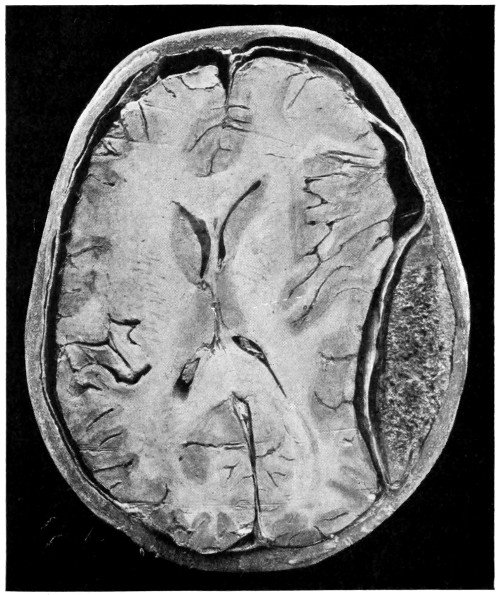

75. A large right-sided temporo-sphenoidal abscess 256

76. To illustrate the pressure effects of a temporo-sphenoidal abscess 257